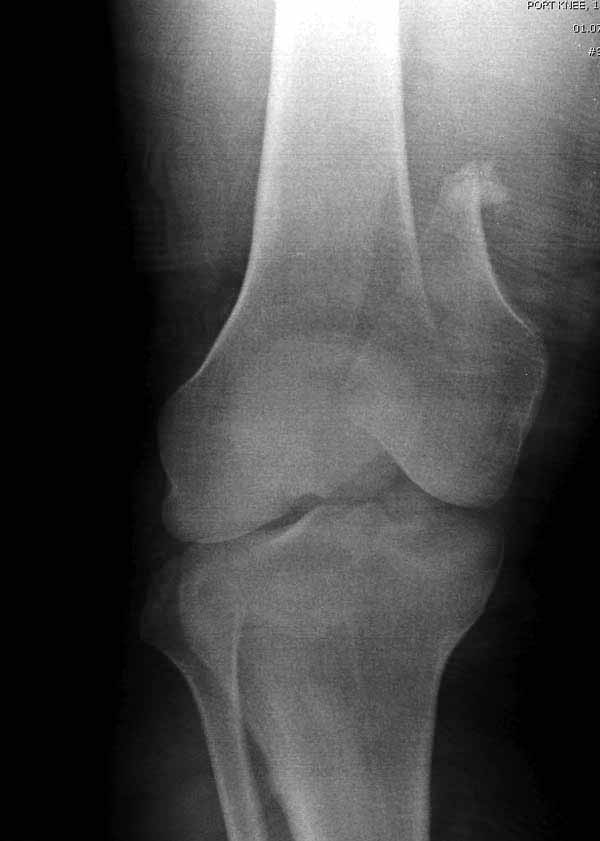

Ответ на эту часть Вашего поста – вложенный файл. Больная оперирована неделю назад по поводу открытого перелома дистального эпиметафиза бедренной кости. После операции она идёт в рентгенкабинет для выполнения послеоперационной контрольной рентгенографии, представленной на слайдах 10 и 11. Узнав, почему её фотографируют, просила передать Вам, Антон, привет.

наружный мыщелок не дорепонироавн - это приводит к вальгусной деформации оси коленного сустава, очень критично для последующей функции.